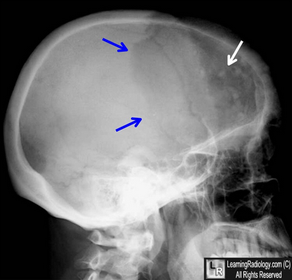

What is shown by the arrows? Lateral skull radiograph shows a large geographic, lytic lesion in the left frontal bone (blue arrows). Also seen are islands of bone (white arrows) producing a "cotton-wool" appearance. Typical in Paget's DS seen in early destructive phase and later mixed stages.